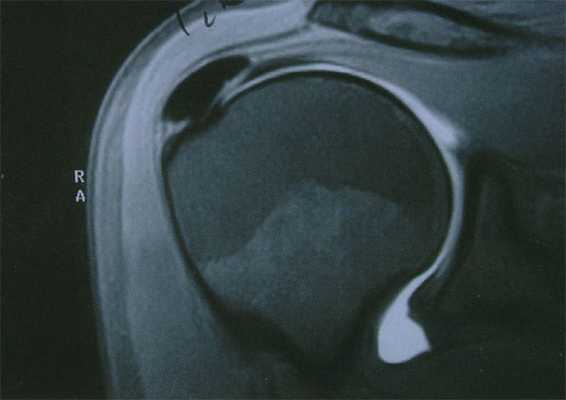

Также в постановке диагноза помогает МРТ исследование.

на МРТ участки кальцификатов отображаются, как отдельные фокусы (очаги) ослабления сигнала